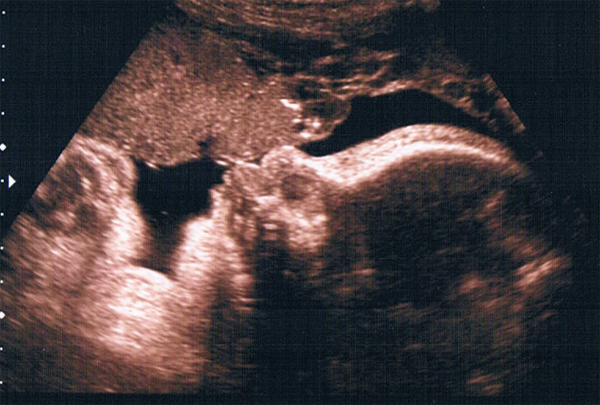

Ultraschallbild vom April 2012 – Coesfelder Krankenhaus